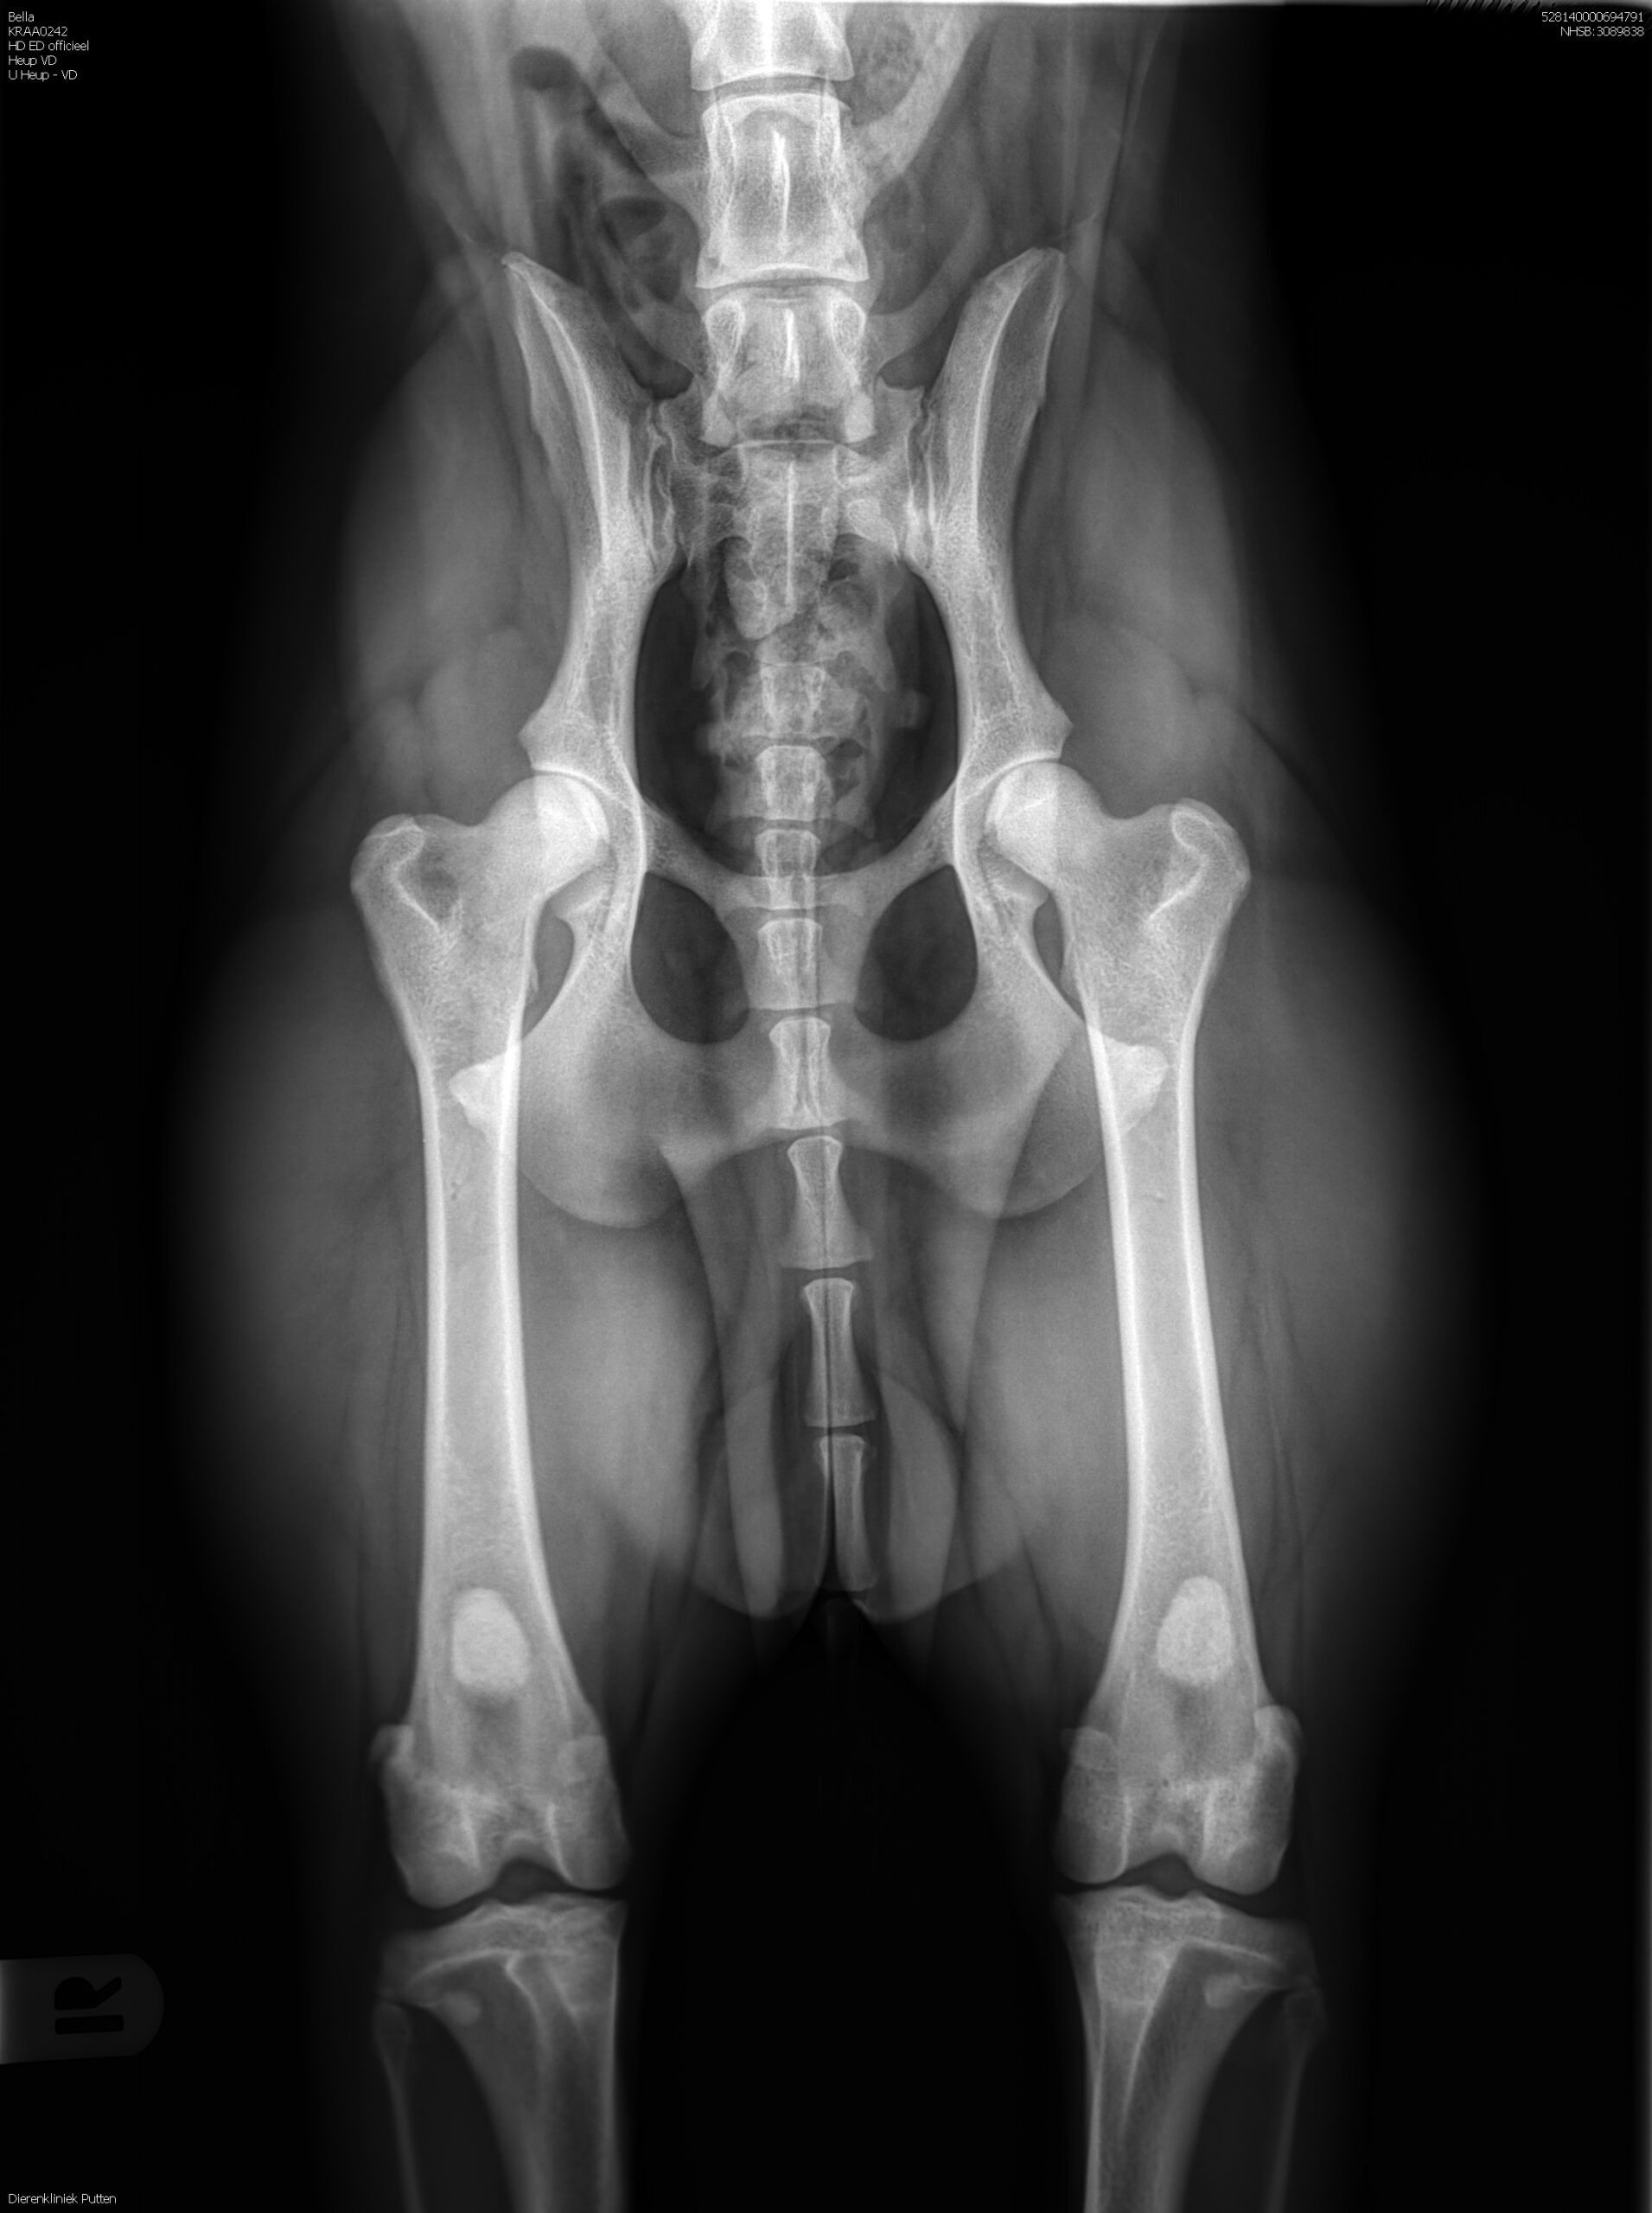

HD-A (Norbergwaarde 37.5, Botafw. 0), ED-0, Rug 100%

Röntgen foto’s Bella